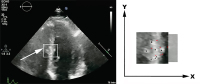

Echo - Myokard-Speckles

Abbildung 1: Ein Muster von Speckles im Myokard wird wie ein Fingerabdruck erfasst. Die räumliche Verlagerung dieses Fingerabdrucks während des Herzzyklus wird von der Software nachverfolgt („getrackt“). Links: Apikaler 4-Kammer-Blick mit Speckle-Muster (Pfeil, weißes Quadrat). Rechts: Verlagerung des Speckle-Musters. Vordergrund: Schwarze Punkte repräsentieren Myokard-Speckles in der Diastole. Hintergrund: Rote Punkte repräsentieren Myokard-Speckles in der Systole